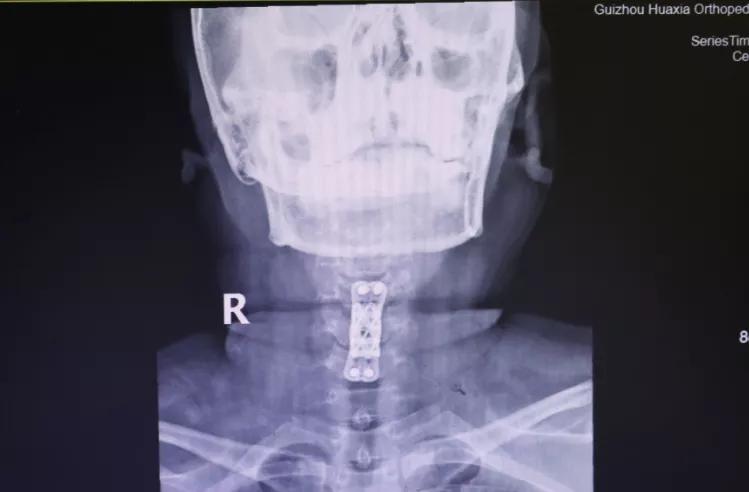

做了全面的检查后,胡阿姨被诊断为:颈椎病(脊髓型);颈椎间盘突出症 ;颈椎后纵带骨化症;肝功能不全 。患者诊断明确,存在明显手术指征,需行手术治疗,进行椎管减压,神经根松解,以阻止病变进一步发展,防止出现更加严重的双下肢瘫痪或大、小便功能障碍。

面对患者严重的病情,为使患者得到最佳、最快的治疗,12月18日,完善术前检查后,为胡阿姨实施了手术治疗。术后,疼痛、麻木等症状大大减轻。

“现在好了很多了,手术很成功。”12月28日,距离手术过去10天,胡阿姨恢复得还不错,心情也变好了。她表示,从医生到护士对病人都很热情,很暖心,谢谢大家。